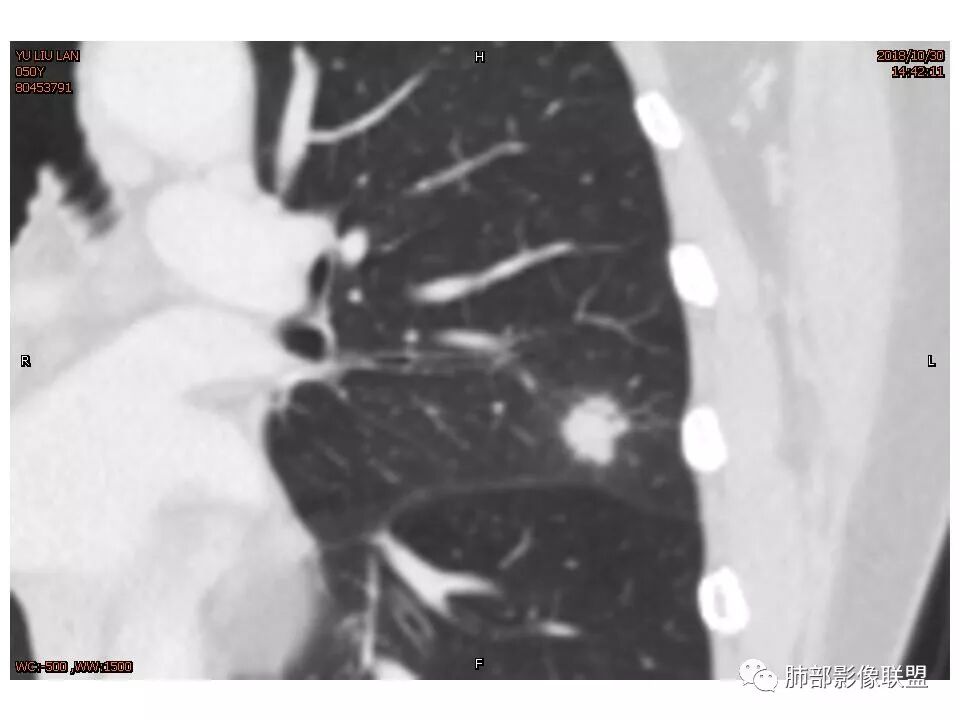

女,50。实性不规则结节,大小12*13mm,分叶、毛刺、胸膜凹陷,牵拉力强,增强渐进性强化,动脉期强化20,静脉期还有进一步强化。边缘强化,点状坏死。

其内血管被破坏。

定位左舌,结节,有晕,晕中软毛刺,长毛刺与胸膜牵拉,收缩明显,部分呈方形,明显强化及延迟强化,有支气管近端进入远端阻塞,部分呈鬼脸

鉴别:腺癌 牵拉斜裂,有动静脉相连,

结节样病灶,u型征,病灶内可见细支气管管,增强可见血管进入,略增粗,病灶周围有晕,有软毛刺,局部叶间胸膜有牵拉,考虑良性炎性病灶,抗炎后复查。

细小毛刺,梳状平行,周围边缘模糊晕,血管未收侵犯,支气管未见牵拉扩张,多条淋巴道与胸膜相联,倾向于炎性病变

1.胸膜下略不规则实性密度结节影,孤立,缺乏典型深分叶,可见淡薄边界模糊磨玻璃晕,可见相对细长软毛刺。

2.如南边老师分析,病灶缺乏边缘膨隆优势,甚至部分平直内收。

3.病灶收缩力不强,整体强化程度不显著。

4.综上,病灶更符合炎性,如隐球菌感染等,而不大符合肺腺癌。具体到机化性肺炎略有些出乎预料。